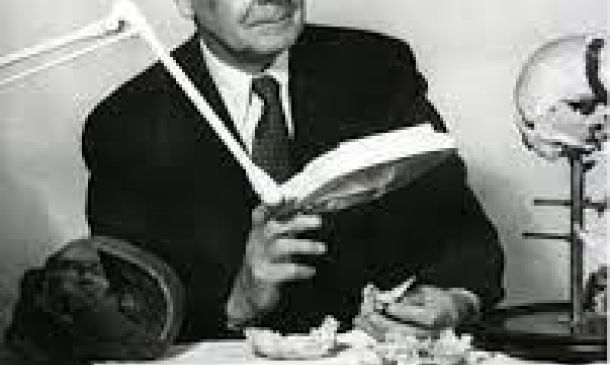

Σύμφωνα με τον Dr. William Garners Sutherland το κρανίο είναι ένας «δυναμικός μηχανισμός» στους ζωντανούς οργανισμούς. Η μελέτη του στις αρχές του 20 αιώνα (1900 – 1954), βασίστηκε στην πολυπλοκότητα της αρχιτεκτονικής των αρθρικών επιφανειών των οστών του κρανίου και του προσώπου.

Ο Dr. Sutherland (1873 – 1954), πατέρας της Κρανιακής Οστεοπαθητικής, παρατήρησε την λειτουργία πέντε βασικών φαινομένων στο ανθρώπινο σώμα. Τα ονόμασε «Τα πέντε φαινόμενα του Πρωτογενή Αναπνευστικού Μηχανισμού».